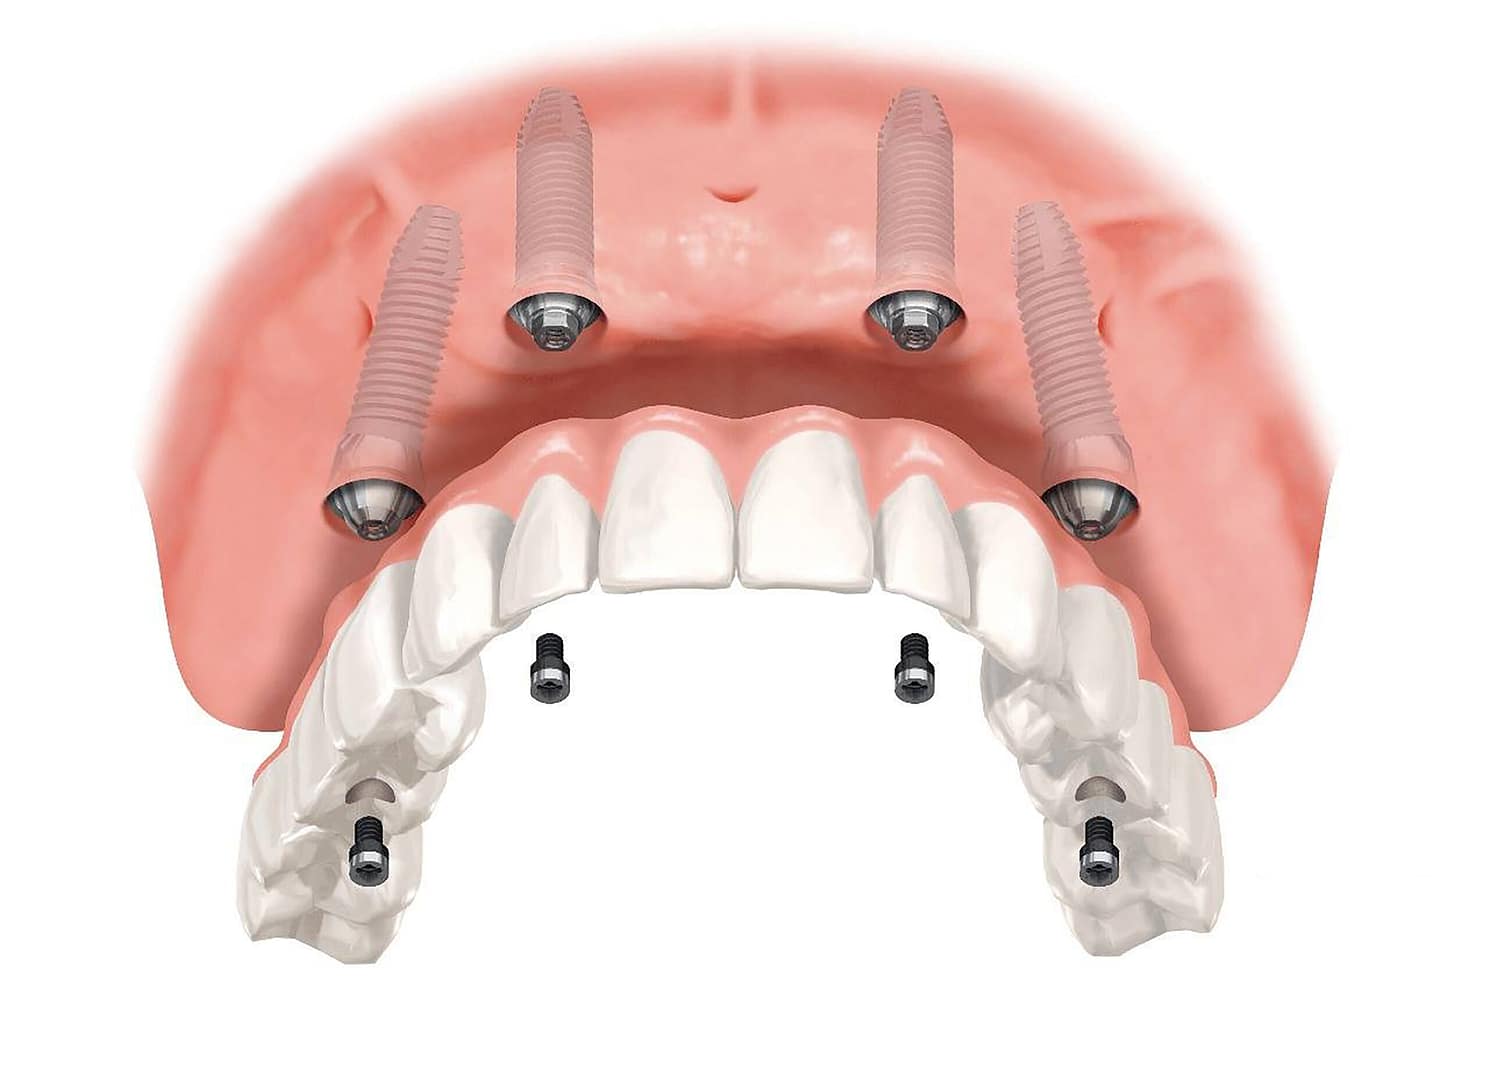

IMPLANTES DENTALES

El implante es una pieza de titanio que se coloca en el hueso como si fuera la raíz del diente perdido. Sobre él se instala una corona que imita la forma y función de un diente natural.